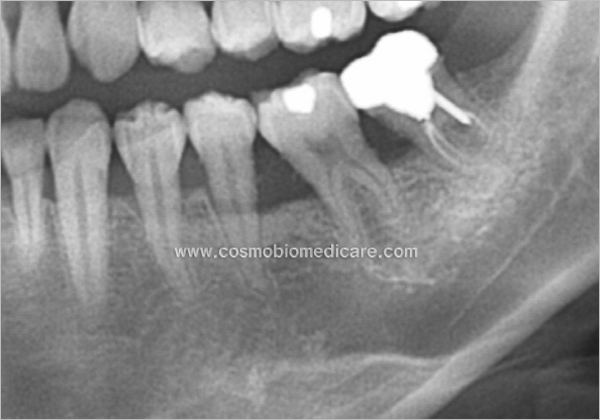

Clinical Cases

• Case1

• Case2

• Case3

• Case4

• Case5

• Case6

• Case7

• Case8

• Case9

• Case10